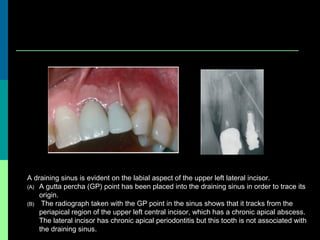

A draining sinus is evident on the labial aspect of the upper left lateral incisor.

(A) A gutta percha (GP) point has been placed into the draining sinus in order to trace its

origin.

(B) The radiograph taken with the GP point in the sinus shows that it tracks from the

periapical region of the upper left central incisor, which has a chronic apical abscess.

The lateral incisor has chronic apical periodontitis but this tooth is not associated with

the draining sinus.